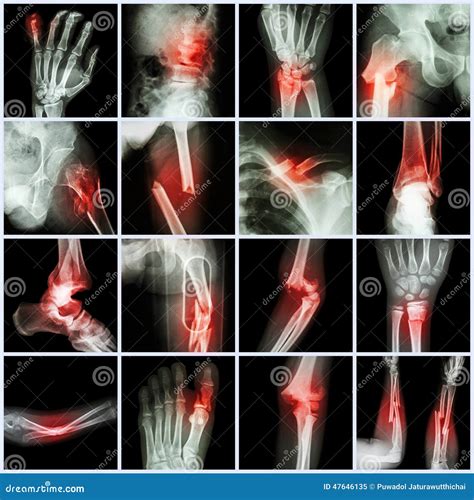

Understanding the intricacies of an Xray of broken bones is crucial for both medical professionals and patients. This diagnostic tool plays a pivotal role in identifying fractures, assessing their severity, and planning appropriate treatment. Whether you are a healthcare provider or someone who has experienced a bone injury, grasping the fundamentals of X-ray imaging can provide valuable insights into the healing process and overall recovery.

When a bone is fractured, the continuity of the bone is disrupted, creating visible gaps or misalignments on the X-ray image. These disruptions can range from simple cracks to complex fractures involving multiple bone fragments. The Xray of broken bones helps medical professionals determine the type and extent of the fracture, which is essential for developing an effective treatment plan.

Fractures can be classified into several types based on their appearance and characteristics. Some of the most common types include:

• Simple Fractures: These are clean breaks where the bone fragments do not pierce the skin.

• Compound Fractures: In these cases, the bone fragments break through the skin, increasing the risk of infection.

• Comminuted Fractures: These involve multiple bone fragments, often requiring surgical intervention.

• Greenstick Fractures: Common in children, these are incomplete fractures where the bone bends but does not break completely.

• Stress Fractures: These are tiny cracks in the bone that develop over time due to repetitive stress or overuse.

Interpreting an Xray of broken bones requires a trained eye and a thorough understanding of bone anatomy. Radiologists look for specific signs of fractures, including:

• Discontinuity of the Bone: Visible gaps or breaks in the bone structure.

• Misalignment: Bones that are not properly aligned, indicating a fracture.

• Overlapping Fragments: Bone fragments that overlap, suggesting a comminuted fracture.

• Soft Tissue Swelling: Swelling around the fracture site, which can indicate the severity of the injury.